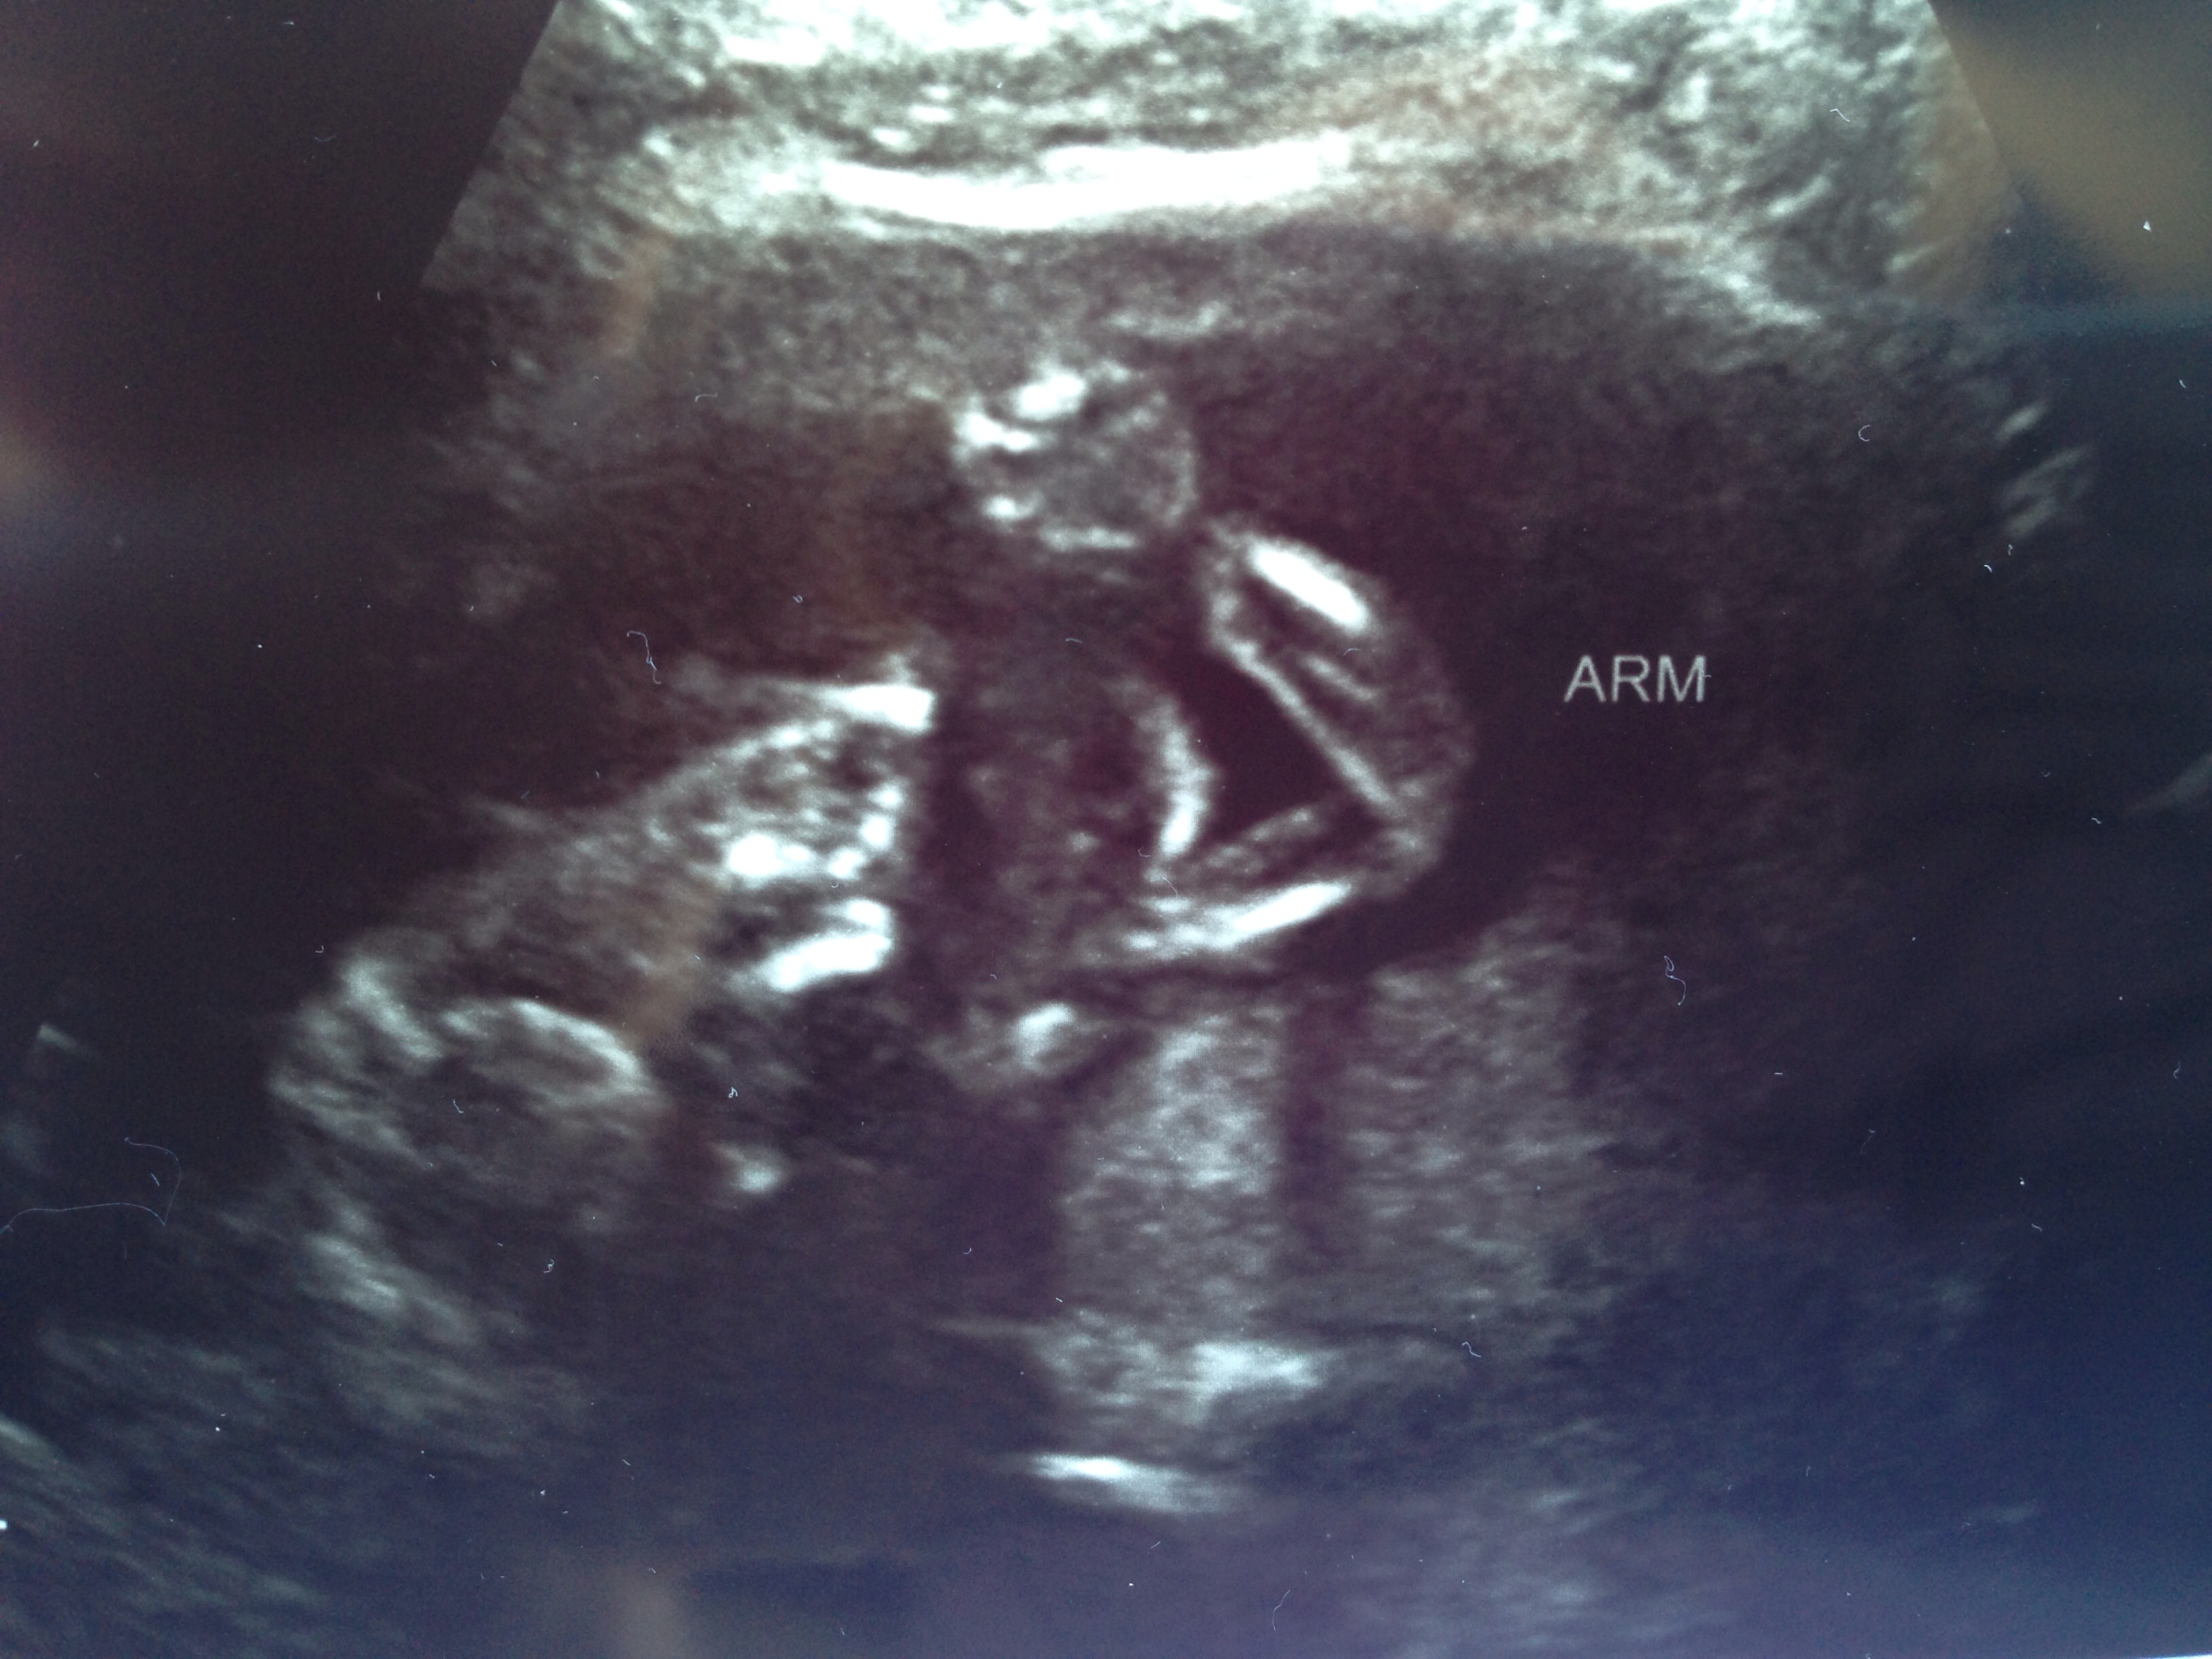

Sorry it's a little late (was busy today). We had A/S today, although we had u/s tech seal it in an envelope. We are finding out gender on Saturday at our reveal party. :-) otherwise baby is doing great. Everything looks and measures good.